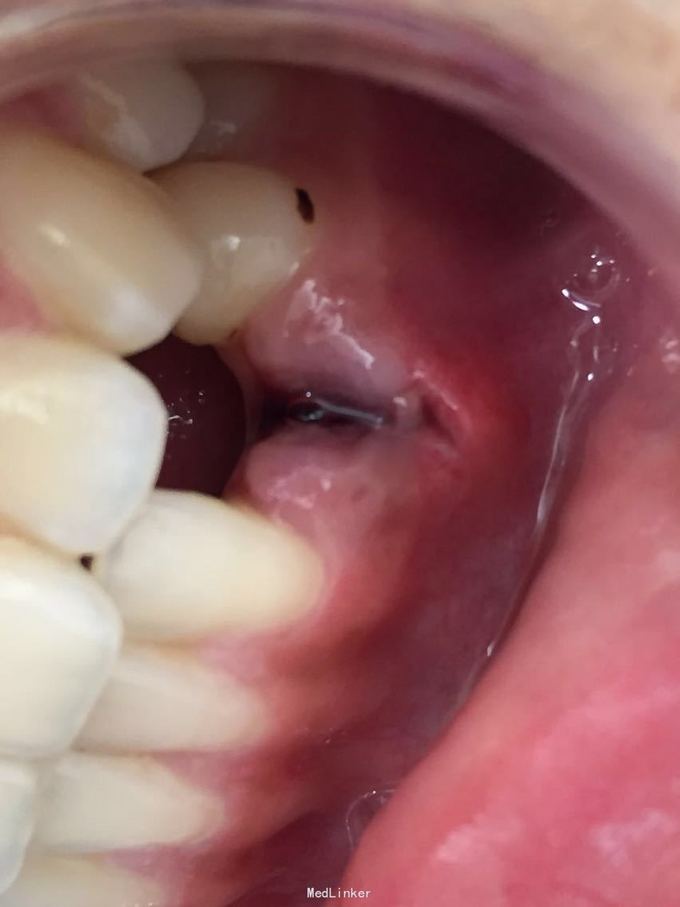

D3完全脱位,伤口血凝块已经凝固,颊侧牙龈钝性撕裂。D2D4无叩痛和松动。脱落牙齿牙体硬组织完好,牙周膜干裂,牙体上有纸屑和食物残渣,根尖有牙髓组织呈黑红色。

D3牙脱位 D3体外根管治疗后垫底充填,盐水和双氧水浸泡后,刮尽牙根的牙周膜后放置盐水和庆大霉素液中15分钟。局麻下刮除牙槽窝内血凝块至流鲜血后盐水和庆大霉素交替冲洗,明胶海绵拭干牙槽窝,浸泡好的牙体植入牙槽窝内并复位,舌侧树脂牙周夹板固定D123456,牙周上派丽奥。随诊